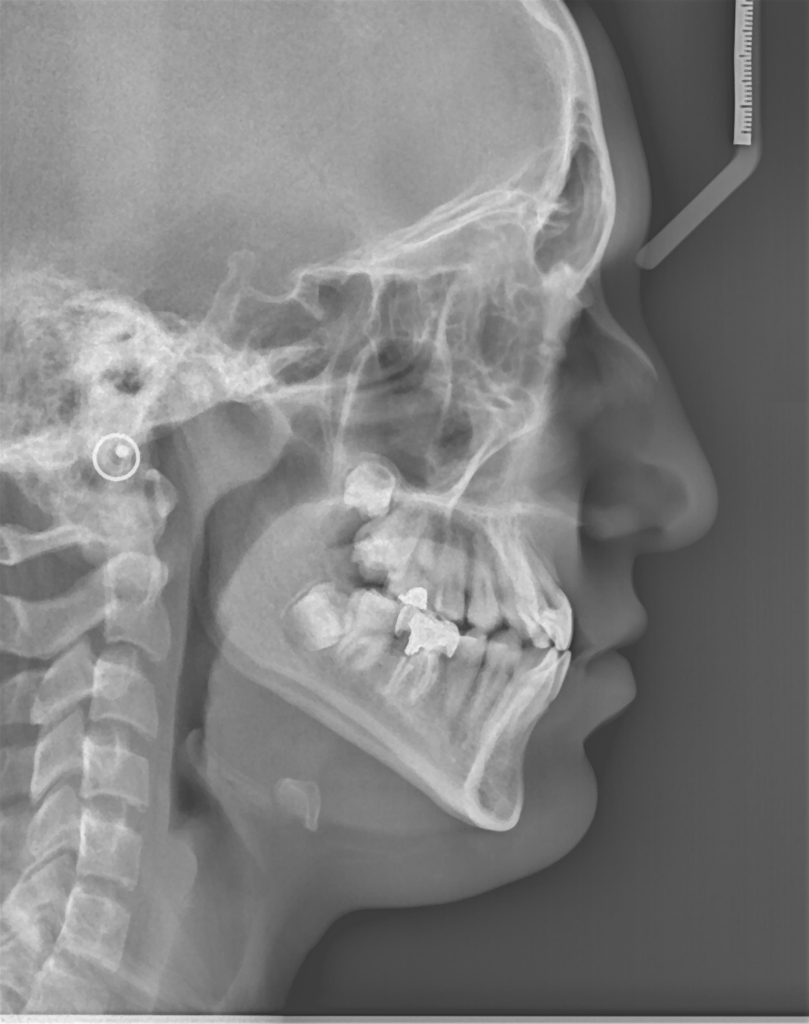

در تشخیص و طرح درمان ناهنجاریهای دندانی – اسکلتی , متخصص ارتودنسی نیاز به روابط فکی و دندانی با استفاده از رادیوگرافی های مناسب دارد.این رادیوگرافیها بطور روتین شامل یک پانورامیک (برای بررسی دندان های از دست رفته, اضافه ,نهفته, جابجا شده و ریشه ها) و یک لترال سفالومتری(برای بررسی روابط فکی و دندانی) می شوند.

آنالیزسفالومتری که بصورت نرم افزاری انجام می شود, در تسریع تشخیص این ناهنجاریها به متخصص ارتودنسی کمک می کند . این رادیوگرافی ها معمولا یکبار قبل از شروع درمان به جهت تشخیص و تعیین پلن درمان و یکبار در طول درمان ویکبار در پایان درمان بمنظور بررسی مسیر درمان و تاثیرات آن تهیه می گردد.